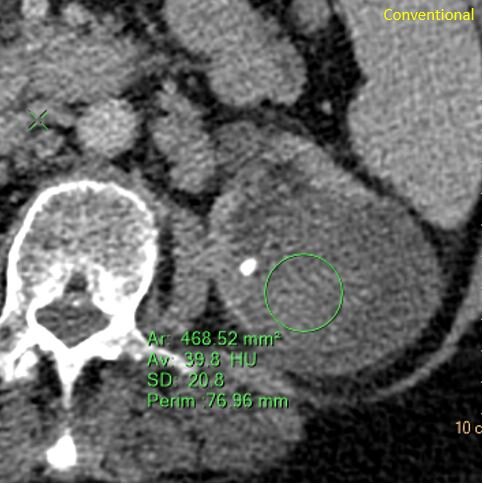

The mixed cystic and solid lesion has a solid component that is about 40 HU in density. On virtual non-contrast this is about 37 HU, so we can say that the solid component shows no enhancement. And there is no iodine uptake in the component. So this is hemorrhage in a cyst. Spectral curves prove this very elegantly.

Conventional CT: Complex cystic and solid mass in left kidney and kidney stone.

Solid component is about 40 HU in density on conventional